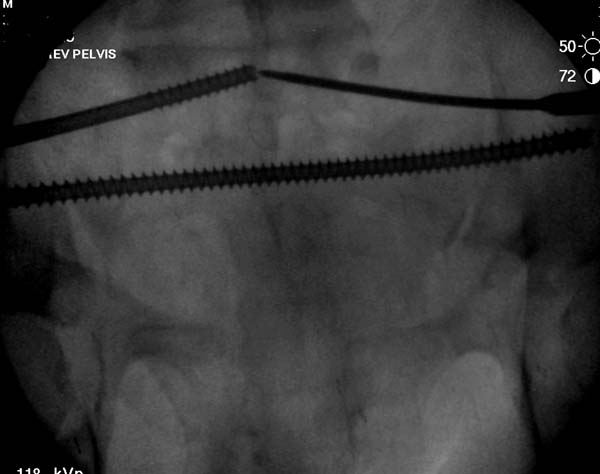

Здесь снимки, которые показывают направление стержня, а также идею

репозиции вытяжением. На рентгенопроницаемых столах имеется возможность

установить дополнительную раму, где по желанию можно увеличить или

уменьшить высоту угла вытяжения. Для репозиции таза больной в положение

на спине, стержень для вытяжения остается во время операции. Система

подойдет для тракции головки бедра из вертлужной впадины, и для этого

стерильная веревка и Synthes Universal Chuck with T-Handle.